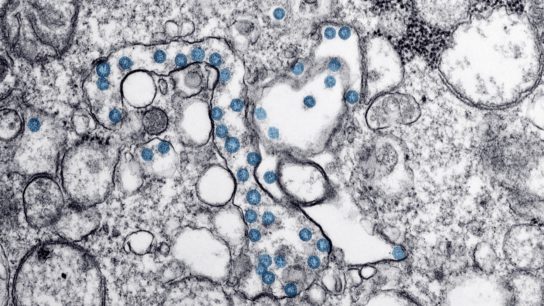

To help clinicians and patients determine if antibodies protect against reinfection, the ACP discussed tests for diagnosing and estimating the prevalence of COVID-19.

Research has revealed that the SARS-CoV-2 viral infection may have neurological manifestations, with critical implications for clinical practice.

Accumulating evidence suggests that COVID-19 can lead to neurological complications.